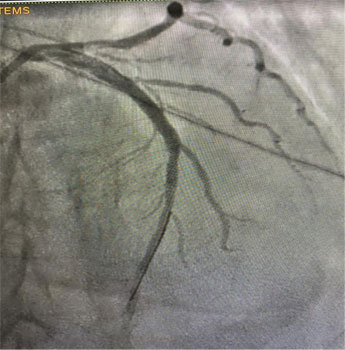

一场与死神争夺生命的战斗拉开了序幕。启动导管室,在呼吸机支持下行急诊冠脉造影,造影过程中患者血压低,生命体征不平稳,紧急植入IABP泵维持患者血压,在IABP泵辅助循环、呼吸机辅助呼吸支持下,成功进行冠脉造影,冠脉造影诊断:冠状动脉双支病变,于罪犯血管LAD植入1枚支架,尝试开通LCX,变换导丝不能通过,考虑LCX为CTO,择期处理LCX病变,植入支架后患者转入重症监护室,经积极治疗成功撤离呼吸机及IABP泵支持后,转至心内科病房,优化药物治疗后,患者病情后好转出院。

术前图